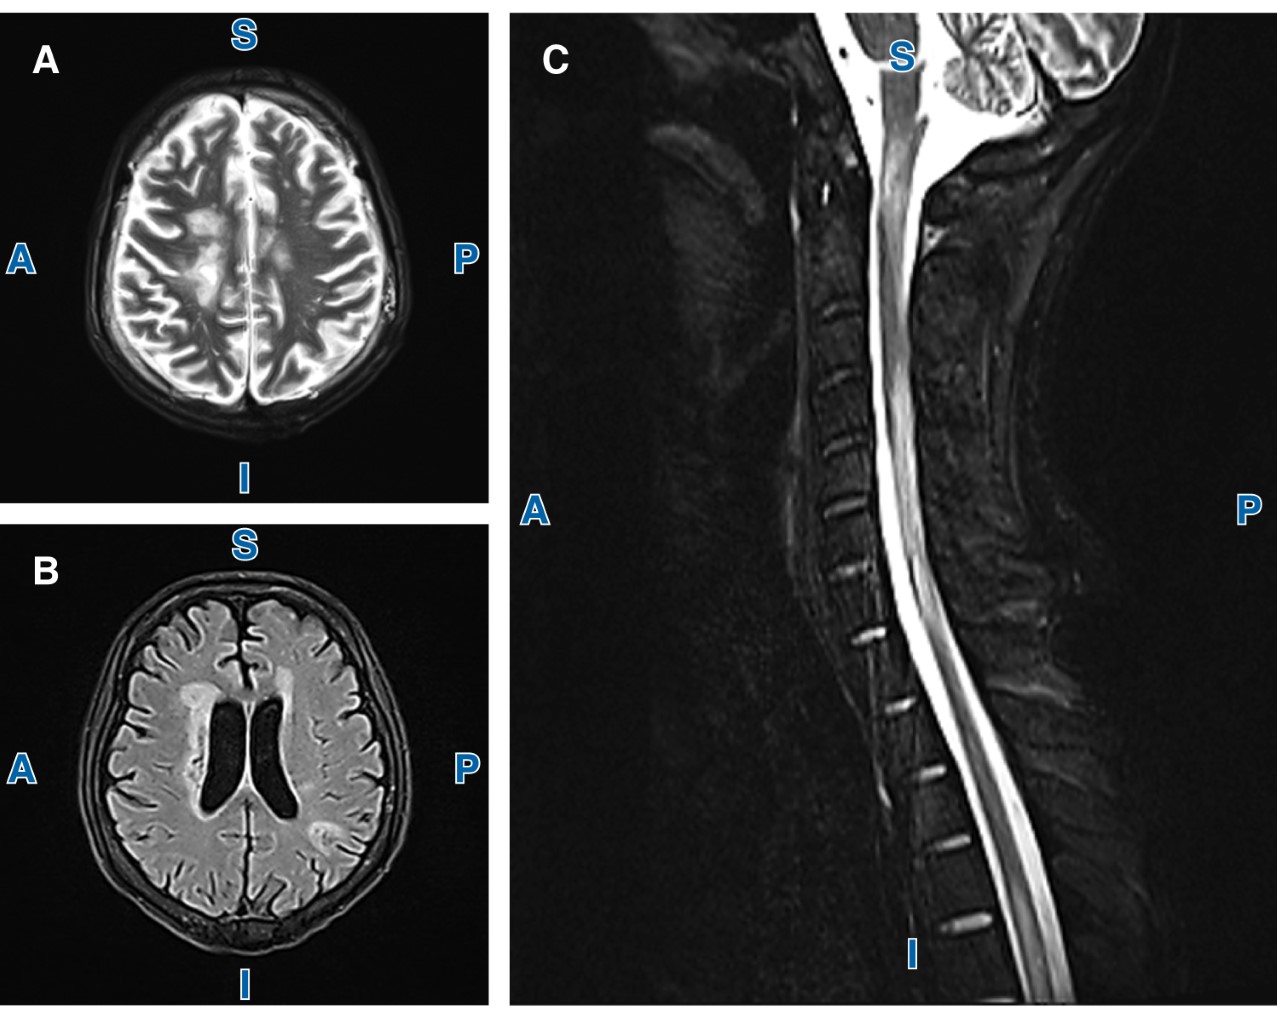

En su IRM cerebral de control el 30 de marzo se observó disminución de las lesiones y menor reforzamiento de las lesiones que previamente presentaban una alta captación de contraste (Figura 3).